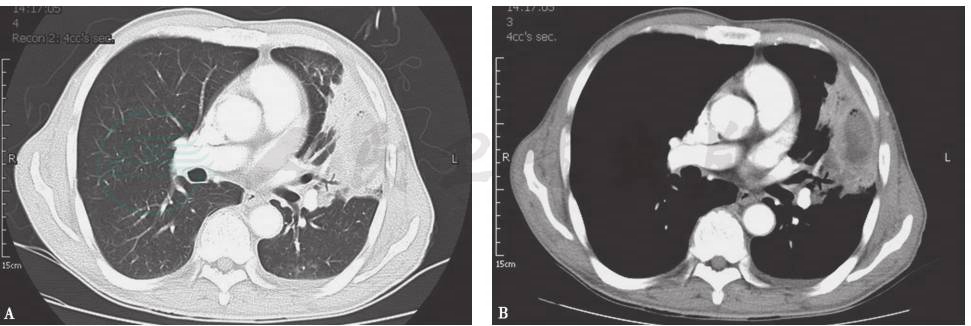

结合患者病史、临床表现及各项检查结果,本病例结核性胸膜炎诊断明确,并且考虑合并结节病。治疗方案采取异烟肼(isoniazid,INH)0.3g(每天1次)、利福平(rifampicin,RFP)0.45g(每天1次)、乙胺丁醇(ethambutol,EMB)0.75g(每天1次)、吡嗪酰胺(pyrazinamide,PZA)0.5g(每天3次)抗结核,同时给予激素治疗。患者症状缓解,出院后亦无不适主诉,坚持2HRZE/10HRE方案抗结核治疗,胸腔积液逐渐吸收。7周后复查胸部CT,发现纵隔淋巴结明显缩小(图13)。正规治疗1年后,患者停药,胸部CT提示纵隔肺门未见明显肿大淋巴结(图14)。

图14 治疗1年后复查胸部CT表现

引自:呼吸系统疑难病例诊疗辨析.第1版.ISBN:978-7-117-26415-0.主编: